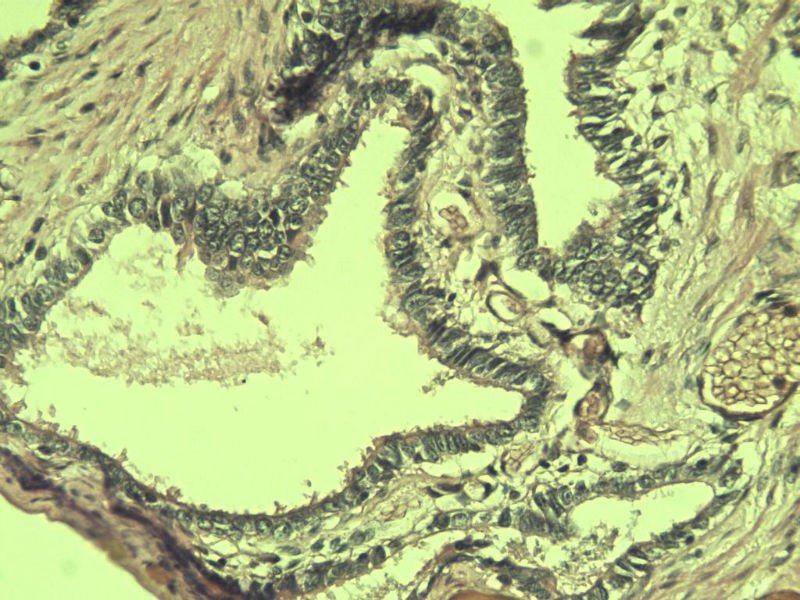

女性患者,42岁 阑尾 大体上看没问题 但是这些东西是什么?? 请指教,谢谢了!